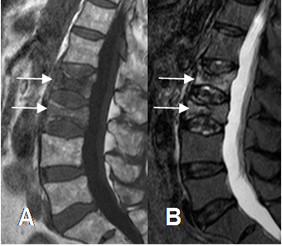

También se puede encontrar acuñamiento anterior de los cuerpos y biconcavidad, por la presión ocasionada por los discos intervertebrales. (Fig 38).

Fig 38. Osteoporosis.

A: RM sagital en T1. Alteración en la SI de los cuerpos de L2 y L3, con configuración en

“ vértebras de pescado”.

B: RM sagital en STIR. Los cuerpos de L2 y L3 son hiperintensos, por fracturas osteoporóticas de evolución reciente.